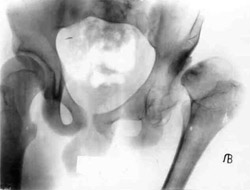

Congenital dislocation of left hip.